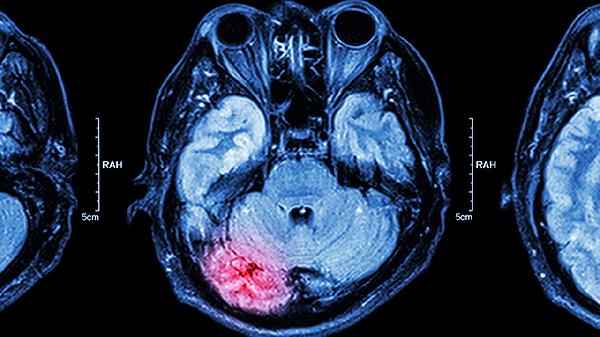

放疗对脑组织的损伤通常与照射野设计密切相关。当肿瘤位置靠近颅底或已侵犯颅内时,放疗计划需覆盖这些区域,可能使部分脑组织受到辐射。常见的损伤包括放射性脑水肿,表现为头痛、恶心或认知功能下降。放射性脑坏死是较严重的并发症,多发生在放疗后数月到数年,可能出现记忆力减退、肢体无力等症状。现代精准放疗技术如调强放疗能显著降低脑组织受量,但完全避免风险仍有难度。

放疗期间及结束后应定期进行头颅核磁共振检查,监测脑组织变化。出现头晕、呕吐或性格改变等症状时需及时就诊。日常注意保持充足睡眠,避免头部剧烈活动,可适当补充维生素E等抗氧化剂。建议在放疗前与肿瘤科医生充分沟通风险,制定个体化防护方案。